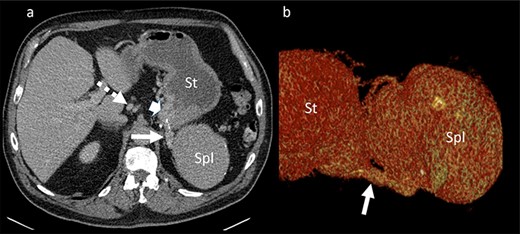

Portal venous phase CT of the upper abdomen (a) with a 3D reconstruction (b); note the gastric varices (arrowhead) and dilatation of short gastric veins (solid arrow) and coronary vein (dashed arrow); St: stomach; Spl: accessory spleen.

was located in the left upper quadrant of the abdomen, nearly adherent to the stomach and a moderate variceal conglomeration in the fundus of the stomach (Fig. 2). Liver cirrhosis or portal vein occlusion and other inflammatory or malignant diseases could be excluded from CT imaging. In addition, a CT scan was able to show clearly that the arterial blood supply of the accessory spleen is derived from the short gastric arteries. Splenic artery and vein could not be delineated. The patient was subsequently presented to our Department of Visceral Surgery. We decided to perform laparoscopic accessory splenectomy to relief the regional hypertension of the short gastric veins. In the operation room, the patient was positioned in right semi-decubitus position. One 12 mm Trocar, two 11 mm Trocars and on 5 mm Trocar were inserted in the left upper quadrant. The accessory spleen was extremely adherent to the diaphragm and retroperitoneal tissue (Fig. 3). After transection of the short gastric vessels with the vessel sealer (Ligasure™, Medtronic, Germany), the spleen was mobilized and removed (Fig. 4). Patient’s postoperative course was completely uneventful, and he was discharged in good health condition on the seventh postoperative day. The diagnosis was confirmed by immunohistologic examination (Fig. 5).